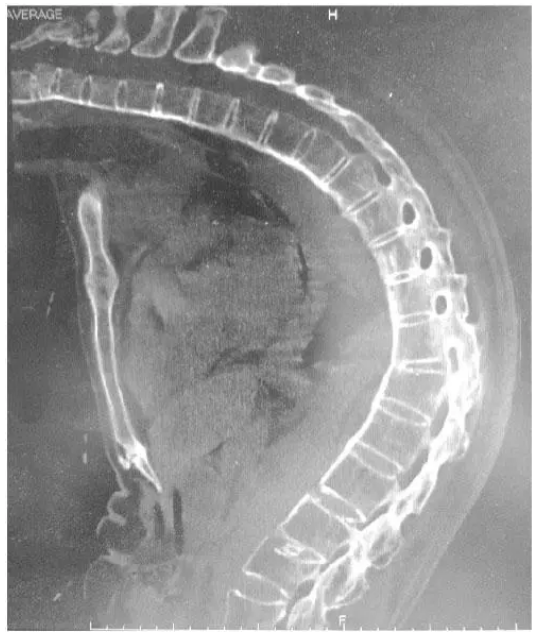

入院颈、胸、腰椎CT示(图2):符合强直性脊柱炎改变,胸12、腰4可见压缩性骨折;肺功能示:轻度限制性通气功能障碍,最大通气量百分率轻度下降,残气占肺总量百分率升高(一口气法),残气量升高,肺总量下降,弥散功能轻度减低;余未见特殊。体格检查:颈部完全不能活动,下颏不能接触胸骨,不能伸颈,下颌前伸能力受限,颞下颌关节活动受限,张口度2.5 cm,甲颏距5 cm。术前充分表麻口腔黏膜下普通喉镜置入口腔后仅可见会厌。麻醉风险评估:已预料的困难气道,患者残气量升高,有效肺泡通气量较少,肺换气功能降低,ASA分级Ⅱ级。

图2 患者胸部CT示